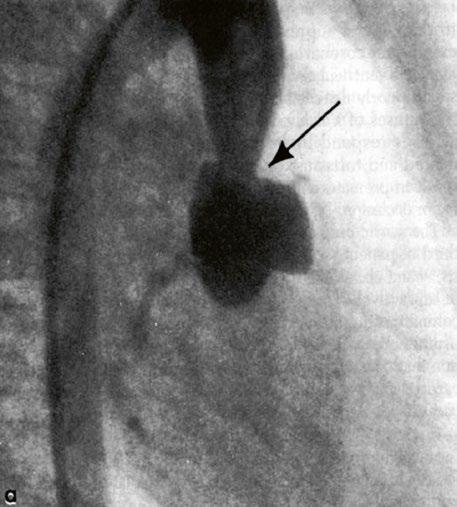

Obr. 45.11 CT angiografie, defekt typu sinus venosus superior je označen hvězdičkou, anomální pravá horní plicní žíla ústící do horní duté žíly je označena šipkou

PS – pravá síň, LS – levá síň